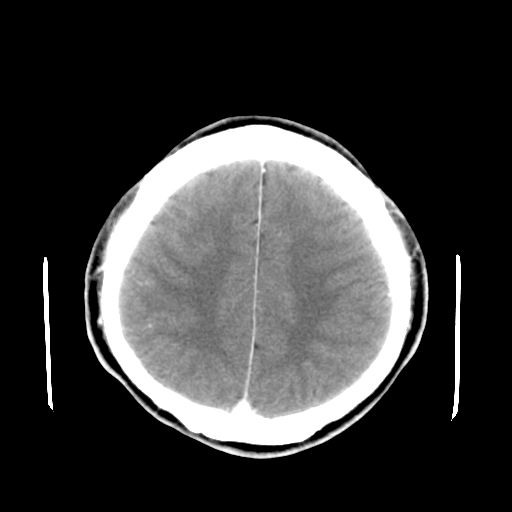

标题: CT16447B:(续)增强扫描图像。 [打印本页]

标题: CT16447B:(续)增强扫描图像。

患者今日做ct增强检查,现补传增强扫描图像。

松果体钙癍增大,无其他改变,定不了性

一般认为大于1cm为异常。